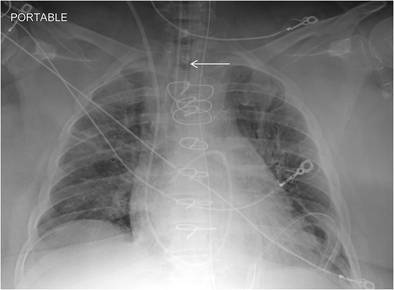

Chest radiograph with ET tube present (white arrow)

Fig. 6

figure 6

Follow-up chest radiograph on the same patient after ET tube has been removed. The white arrow depicts the absence of the ET tube